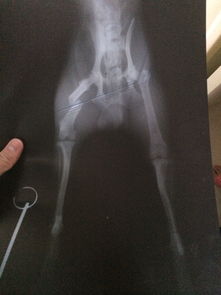

看了你追加描述和圖片,基本確定是骨折!不打算去醫(yī)院的話就按照我上面說的做,狠狠心找到骨折的地方,試著做一下整復(fù),外邊用硬紙殼固定!可以去買一些人藥!狗狗會(huì)很快好起來的

哎。我家就是。大年三十那天自己從沙發(fā)跳下來以后,前腿一只就不粘地了,嗷嗷嗷的叫了半天。剛開始走路都不會(huì)了。三條腿不習(xí)慣,正好趕上過年,寵物醫(yī)院什么的也不方便.我摸了摸骨頭,沒什么異常..也沒固定,以為第2天能好,結(jié)果第2天只3條腿走路??蛇^年沒人啊。等3天左右吧,發(fā)現(xiàn)前腿直的那條骨頭居然像V字一樣突起了..我期間一直喂的紅藥。.

給醫(yī)院打電話,說內(nèi)固定3000。外固定700左右。有點(diǎn)貴。家人不同意我治。狗花4000買的- -!說不想再花錢勒。..我只好自己給做了個(gè)外固定,用雪糕棍什么的。..

到現(xiàn)在,1個(gè)多月過去了。.跑跳都可以了.就是那腿,還是沒直。..看樣子也是直不了啦。.我就一直外固定呢。.還好沒影響到它什么。長短腿了。..

你如果有條件,最好帶醫(yī)生那里,把骨頭位置掰正!讓受傷部位對(duì)齊.然后自己做外固定長好!我家就沒對(duì)齊,直接外固定了,,,,哎。沒辦法。.